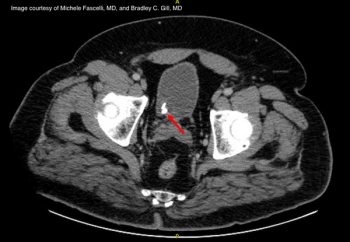

An elderly male with hypertension, lumbar spinal stenosis, morbid obesity, and ED presents with acute right-sided worsening of his chronic back pain. A distal right ureteral stone is found on CT and his symptoms respond well to medical therapy, but he later develops severe right flank pain.